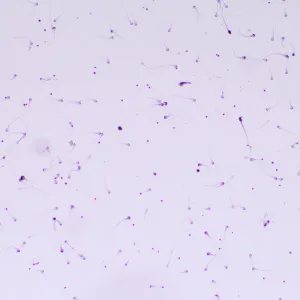

Микроскоп MAGUS Bio 260T – рутинный, с ним можно проводить лабораторные и научные исследования, или использовать его для учебного процесса. Микроскоп работает с тонкими прозрачными и полупрозрачными препаратами в светлом поле. Однако на прибор можно поставить дополнительные компоненты, которые расширят его возможности для проведения исследований по методам темного поля, фазового контраста, в поляризованном и люминесцентном свете.

Дополнительные элементы расширят функционал прибора. Набор окуляров увеличит спектр увеличения. Для дополнительных методов работы с препаратами, которые невозможно рассмотреть в светлом поле, нужно дополнить микроскоп фазово-контрастным устройством, слайдером темного поля или устройством простой поляризации. Цифровая камера поможет зафиксировать на фото или видео результаты исследования или выведет картинку на экран. Измерить объекты можно, применяя калибровочный слайд вместе с окуляром со шкалой или с цифровой камерой.